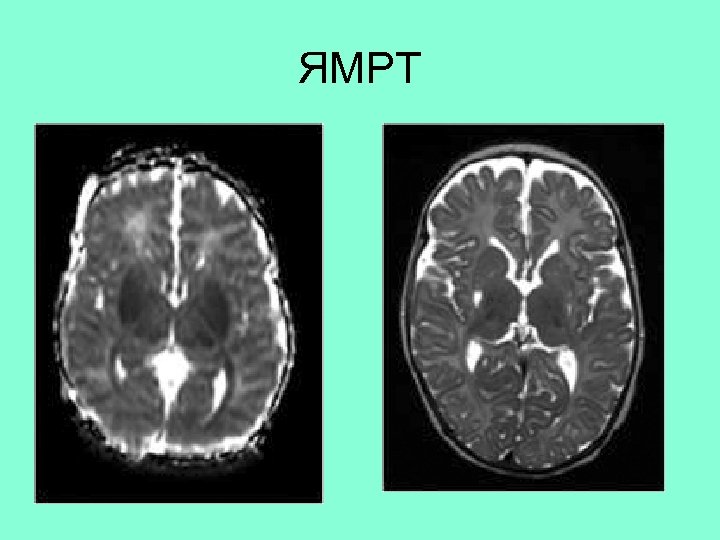

25 недель ГВ, БЛД • А – высокоинтенсивный сигнал в центральном белом веществе • В – сигнал низкой интенсивности в центральном белом веществе характеризующий диффузное поражение белого вещества

ЯМРТ